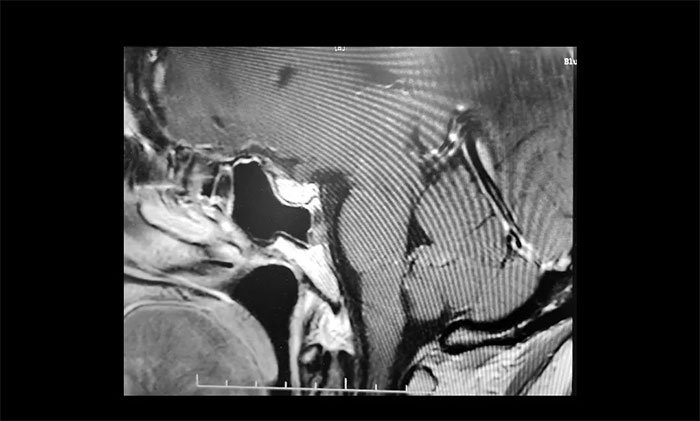

▲ 术后影像显示肿瘤被切除

术中,在蔡司显微镜(双荧光)下,见肿瘤组织包绕左侧嗅神经,双侧视神经被生发于鞍结节处的肿瘤组织挤压至外下方,且与肿瘤组织关系密切。李士其教授处之泰然,在充分保护好重要血管神经的前提下,逐步将肿瘤与周围的神经、血管一点点分离开来,分块切除肿瘤,让视神经得到了充分减压。历时3个多小时,手术终于顺利完成。